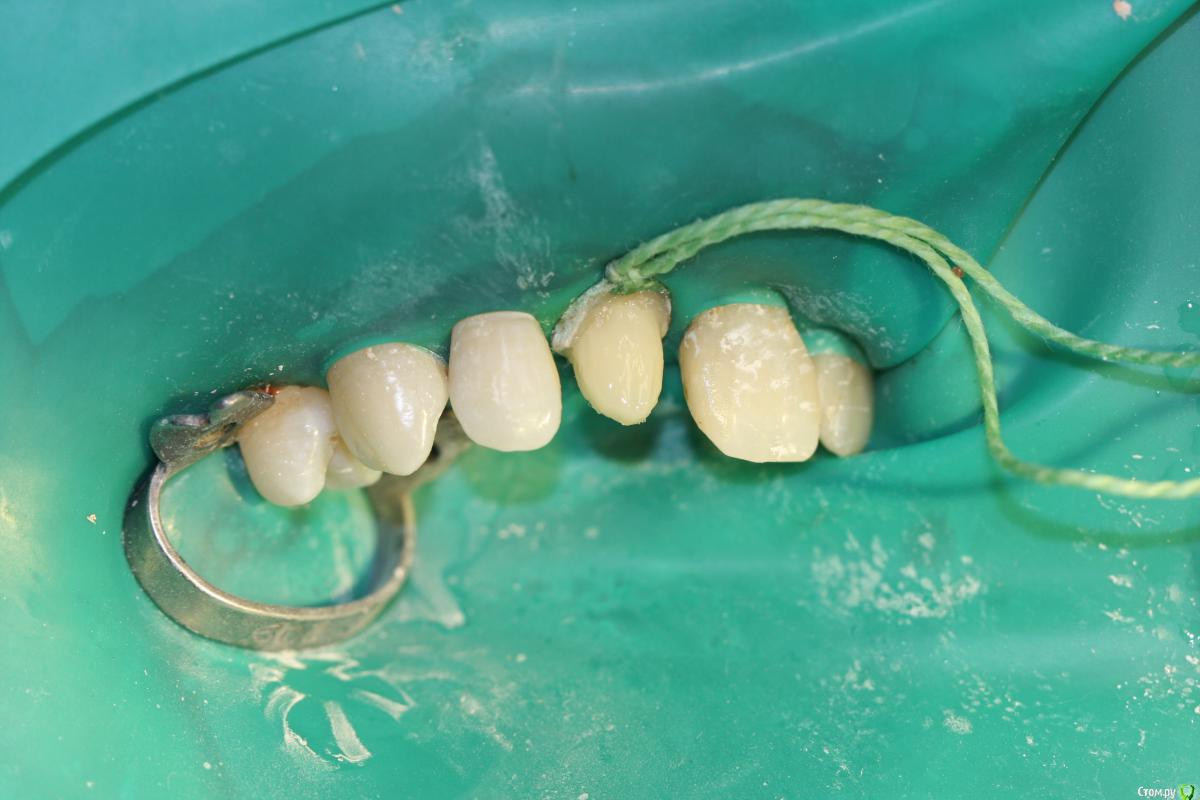

skeettrap Опубликовано 19 марта, 2016 Поделиться Опубликовано 19 марта, 2016 Работа из категории - для души. Попутно сделан кариес у 12 с медиальной стенки , 21 - только подполирована медиальная стенка. 3 Ссылка на комментарий

skeettrap Опубликовано 22 марта, 2016 Автор Поделиться Опубликовано 22 марта, 2016 У Вас хорошо получилось, каким материалом восстанавливали? Только не поняла, почему сразу кламп не надели?удобнее было бы, имхо.Спасибо. Материал Filtek Supreme. Без клампа удобнее восстанавливать контактные и небную стенки, а с ним удобнее пришейку. Ссылка на комментарий